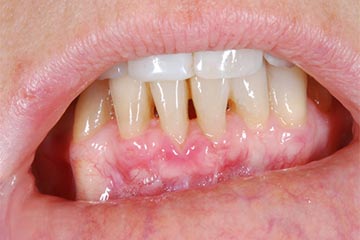

I denti irrecuperabili dell'arcata superiore ed inferiore del paziente di anni 65

sono stati sostituiti da 10 impianti, cioè protesi radicolari endo-ossee che sostengono le protesi fisse superiore ed inferiore.